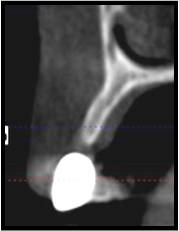

This CT scan shows the amount of bone that can be gained using bone grafting procedures.

After